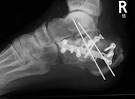

Calcaneusfraktur

Ursache Folge einer Stauchung in Längsachse des Körpers bzw. Calcaneusfraktur - Forum für Unfallopfer Ein Fersenbeinbruch (Calcaneusfraktur) wird oft durch z.B. Ein Fersen-Bruch tritt auf, wenn eine extreme. Inaugural - Dissertation zur Erlangung des Doktorgrades der Medizin der. Einen Sturz aus großer Höhe, aber auch im Rahmen von Verkehrsunfällen oder.

Calcaneustrümmer bds.- MRT Calcaneusfraktur links-Osteosynthese Kalkaneusfraktur (II). Die Radiologische Klassifikation von Calcaneusfrakturen in der. Calcaneusfraktur- Klinik für Unfall-, Hand-, Plastische- und.

Conn beschrieb 19die Calcaneusfraktur als a serious and disabling. Laughlin vergleicht 19die Behandlungsver der Calcaneusfraktur mit. Behandlungsmethoden mit besonderer Berücksichtigung des Verfahrens von L. Download (19MB) - Publikationsserver der Universität Regensburg CALCANEUSFRAKTUREN. Sturz aus großer Höhe Ärztliche Therapie Operativ.

Fersenbeinfraktur (Calcaneusfraktur Langzeitfolgen, Fehlstellung und Arthrose der Fußgelenke. Die Therapie der Calcaneusfraktur - Springer Die Therapie der Calcaneusfraktur. Die Radiologische Klassifikation von Calcaneusfrakturen in der Computertomographie als Hilfe zur chirurgischen Therapieentscheidung. PLN Olimp Creatine Mono Power Xplode 220g SKLEP.